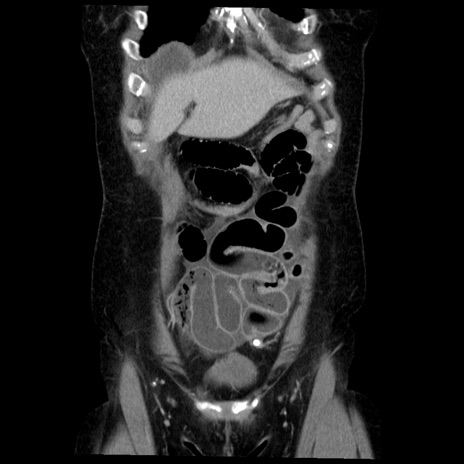

症例6(冠状断像)

【症例】50歳代女性

【主訴】下腹部痛

【現病歴】本日朝より下痢2回あり。 昼食を食べた後、嘔吐3回、下腹部痛認め、症状軽快せず、当院救急搬送。

最終食事:本日昼(生ものなし)。 昨日の夜、刺身を食ぺたとのこと。周囲に同様の症状の者なし。普段、排便は毎日あるとのこと。

【既往歴】卵巣癌術後(8年前に当院で卵巣摘出)

【身体所見】 意識清明、腹部:平坦、腸蠕動音→、やや硬、下腹部自発痛・圧痛あり、反跳痛あり、筋性防御なし。

【データ】WBC 16000、CRP 0.01